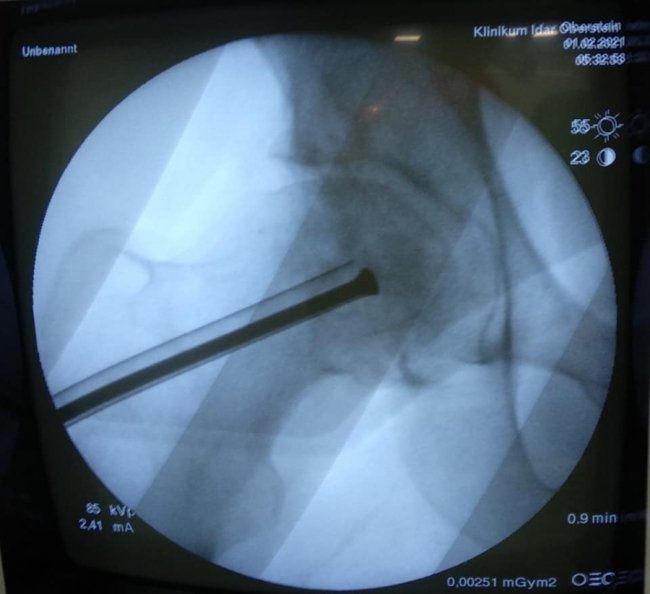

В ході подальшого дослідження в головці правої стегнової кістки виявили кисту розмірами 2*2*2,5 см.

"В ході клінічного розбору було прийняте рішення на користь органозберігаючої операції. Куратор напрямку пухлин та пухлиноподібних захворювань Шевчик Я.В. виконав унікальну операцію: декомпресійну пластику кисти головки стегнової кістки", - йдеться в дописі.

Ця операція полягає у видаленні вмісту кисти, очищенні її стінок та виповнення дефекту кістковим трансплантатом з доступу розміром 3 см.

Перевагами цього методу є – збереження суглоба пацієнта, малоінвазивність та рання мобілізація з максимально швидким поверненням до повноцінного життя.